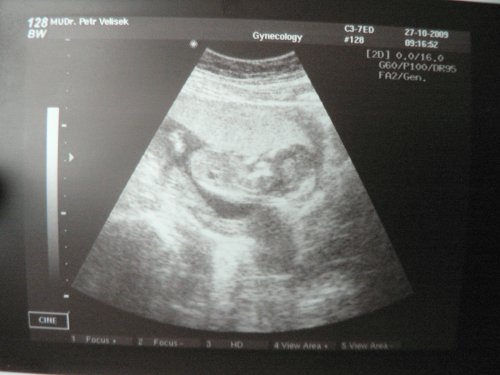

V úterý 27.4.2010 jsem nastoupila do porodnice v Písku. Byla jsem 2 dny po termínu. Jelikož jsme poslední měsíc těhotenství měla hypertenzi, byla jsem přijata pro indukci porodu. Byla jsem vyšetřena (otevřená na necelé 2cm) , udělali mi monitor a UTZ (odhad 3500g). A začala jsem od 10 hodin sbírat moč na bílkovinu, kterou jsem sbírala 24 hodin. Jinak se nic jiného nedělo....